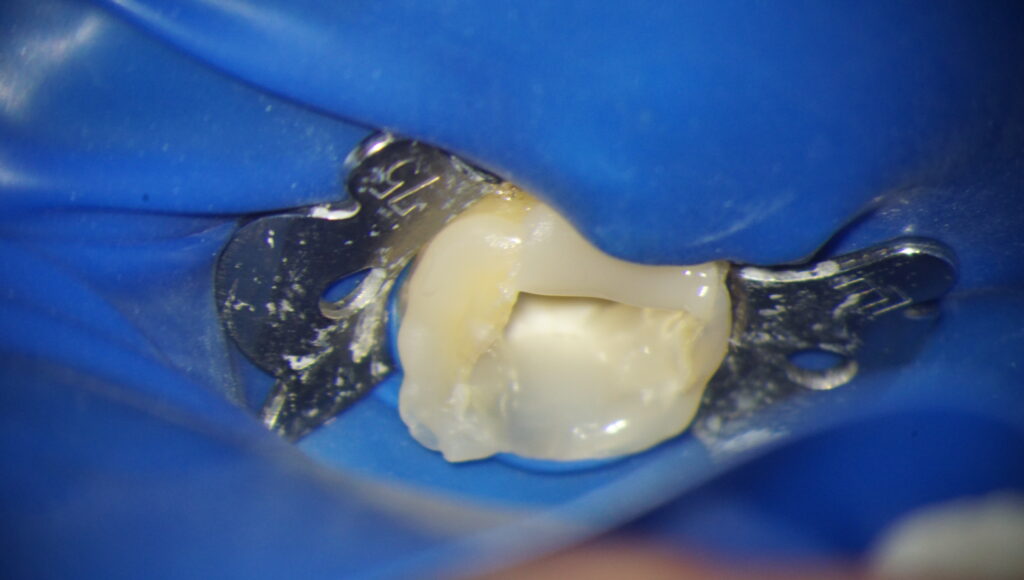

改変したら、ラバーダムをかけることができます。

次回より、根管内部を治療していきます。